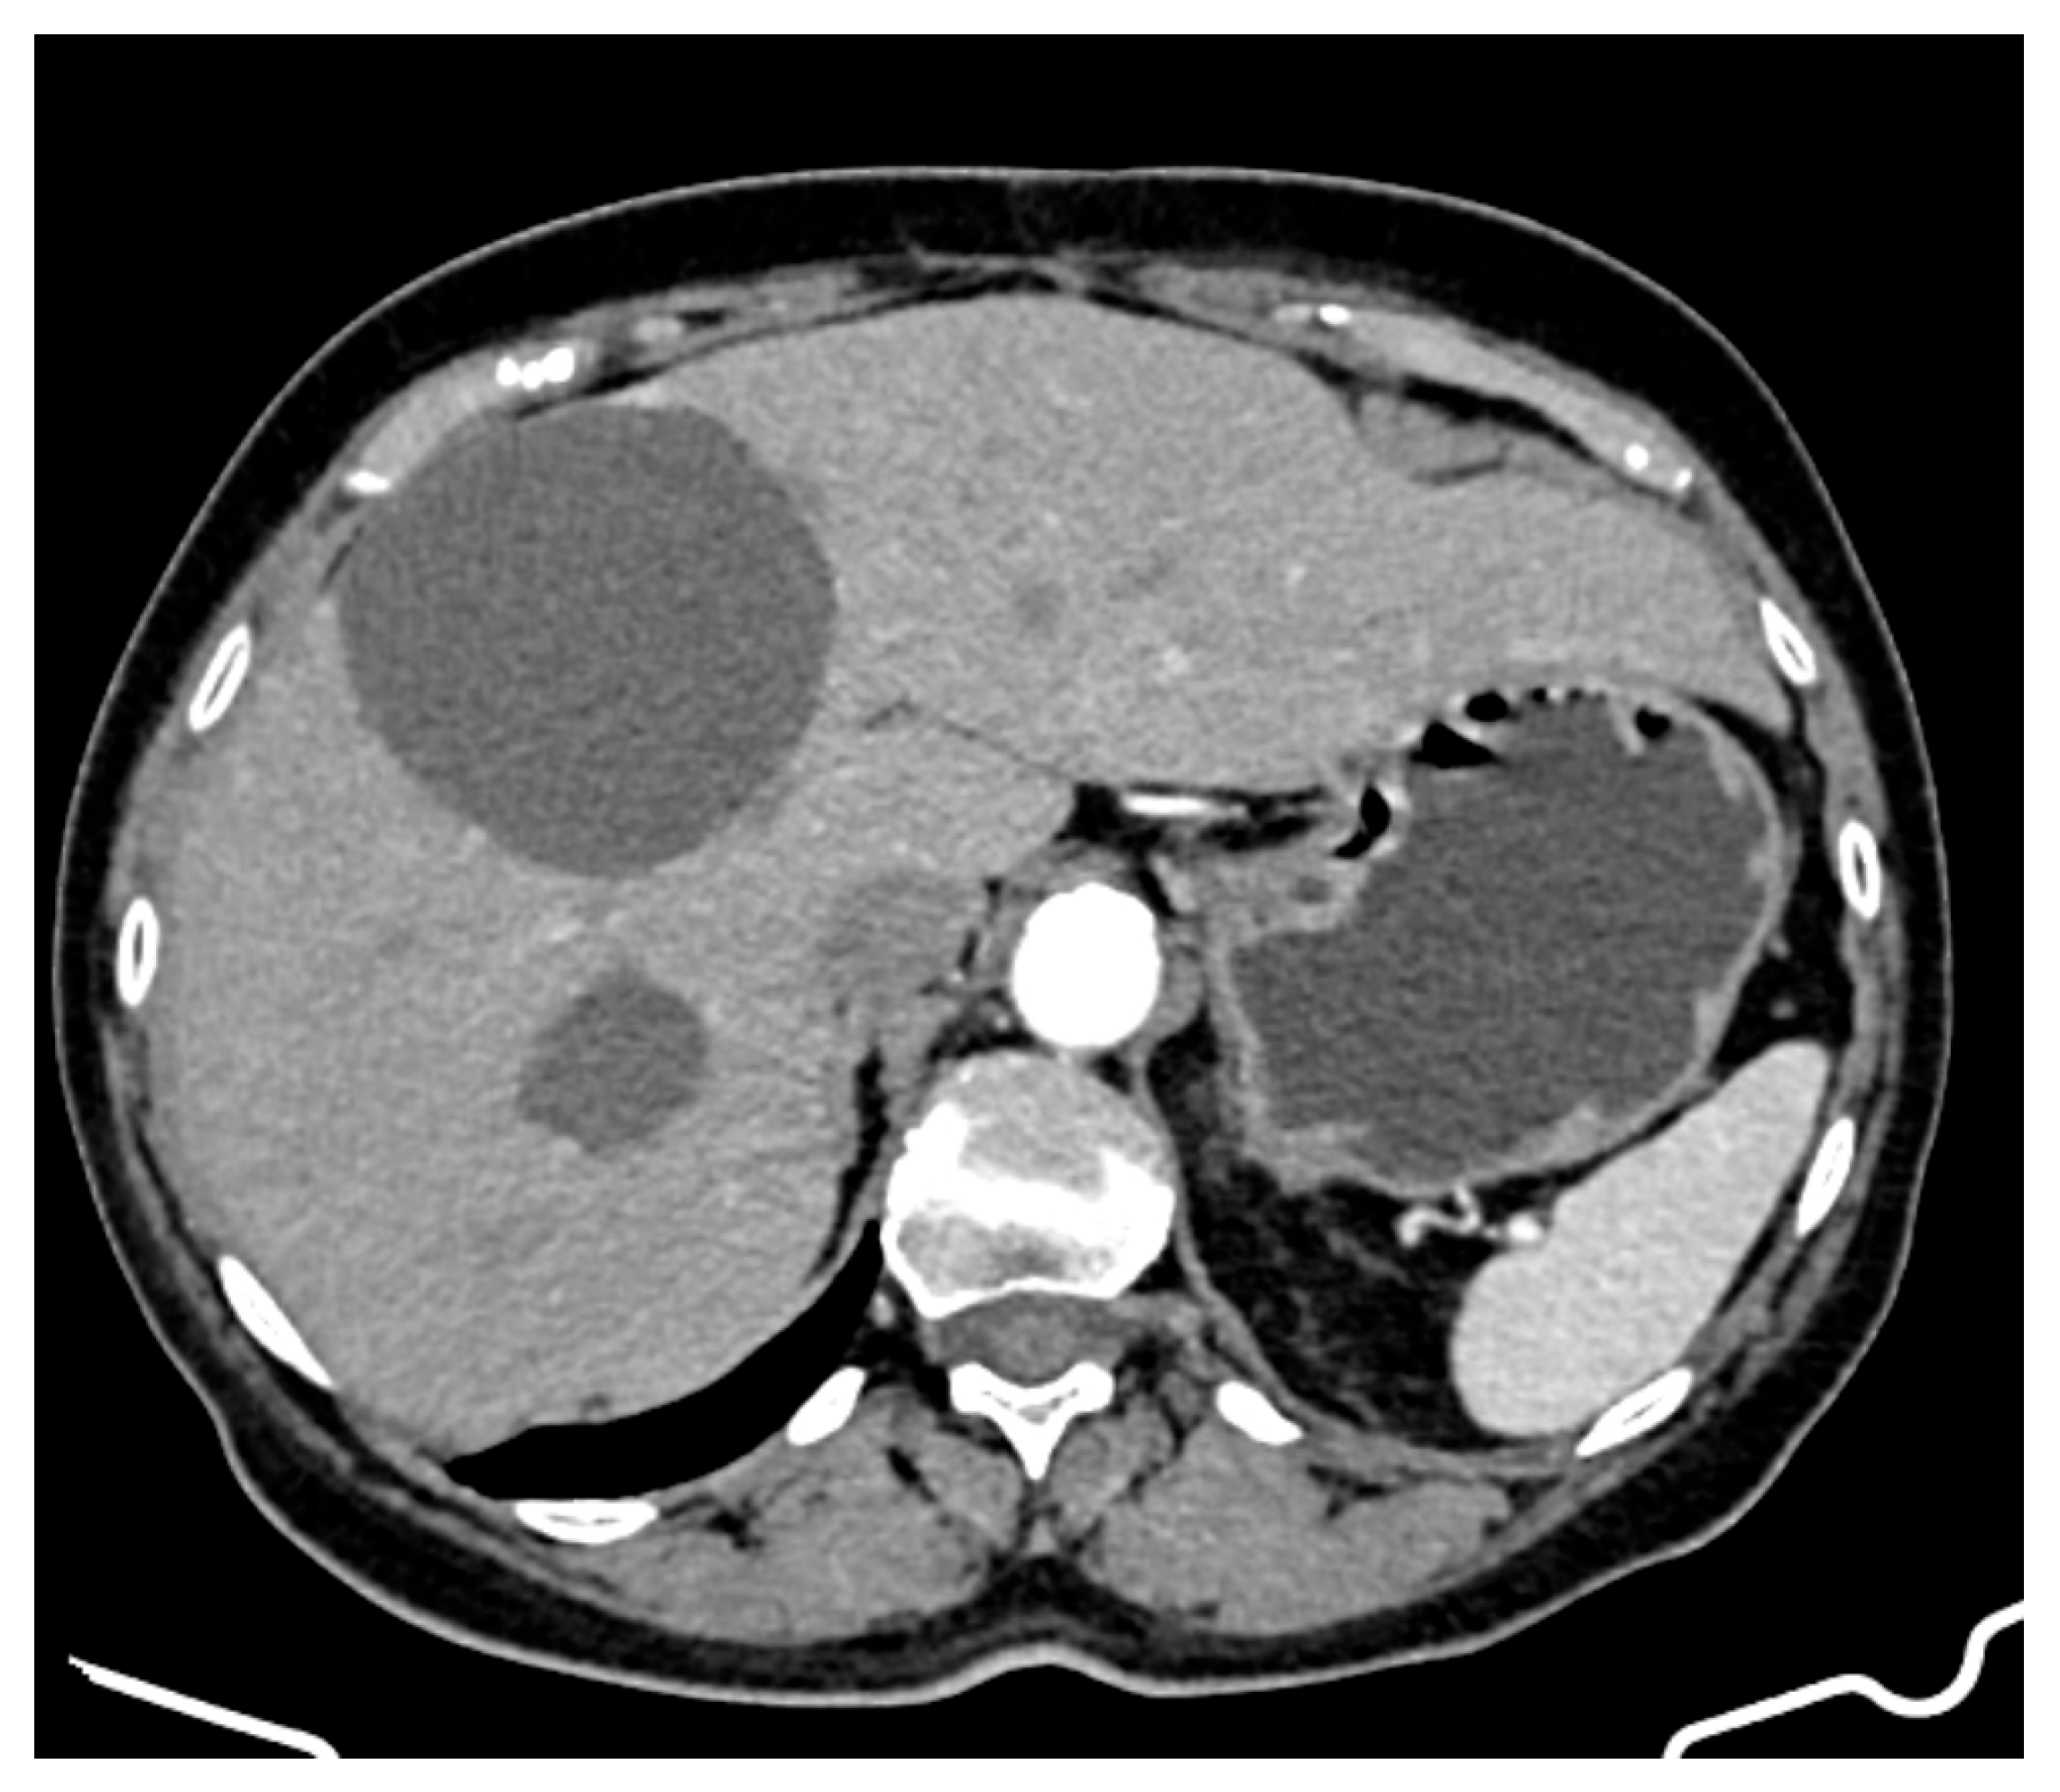

A CT evaluation after 7 months of sunitinib therapy showed stable hepatic disease, with no new metastatic lesions (Figure 4). However, the patient experienced significant side effects, including Grade 3 neutropenia and hypertension, leading to temporary treatment interruptions. Other reported side effects included cataract development, complete nail bed dekeratinization of the toes, and persistent anaemia, for which she received supportive therapy.

Figure 4.

CT appearance at 7 months of treatment with sunitinib.

At 20 months on sunitinib (85 months post-diagnosis), a new cystic lesion in segment VII was detected, raising concerns about treatment resistance (Figure 5). While some known lesions had slightly decreased in size, the emergence of this new lesion indicated ongoing tumour activity that required close monitoring and possible re-evaluation of the treatment strategy.

Figure 5.

CT appearance at 20 months of treatment with sunitinib.